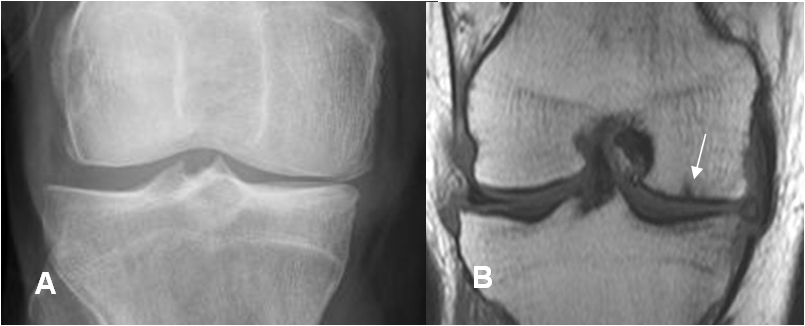

Un dato clave, es que la disminución del espacio articular es no uniforme o asimétrico. El ejemplo típico es la rodilla, donde los cambios muestran predominio del compartimiento medial y la articulación patelofemoral. (3). (Fig 9 y 10).

Fig 9. Artropatía degenerativa.

A: Rx AP y B: RM T1 coronal. Compromiso asimétrico del compartimiento medial, con erosión articular. (Flecha).